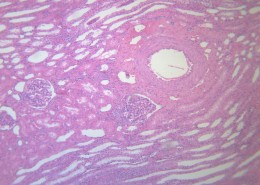

肺水肿(pulmonaryedema)是肺脏内血管与组织之间液体交换功能紊乱所致的肺含水量增加本病可严重影响呼吸功能,是临床上较常见的急性呼吸衰竭的病因。主要临床表现为极度呼吸困难,端坐呼吸,紫绀,大汗淋漓,阵发性咳嗽伴大量白色或粉红色泡沫痰,双肺布满对称性湿啰音,X线胸片可见两肺蝶形片状模糊阴影,晚期可出现休克甚至死亡。动脉血气分析早期可有低O2、低CO2分压、严重缺O2、CO2 潴留及混合性酸中毒。